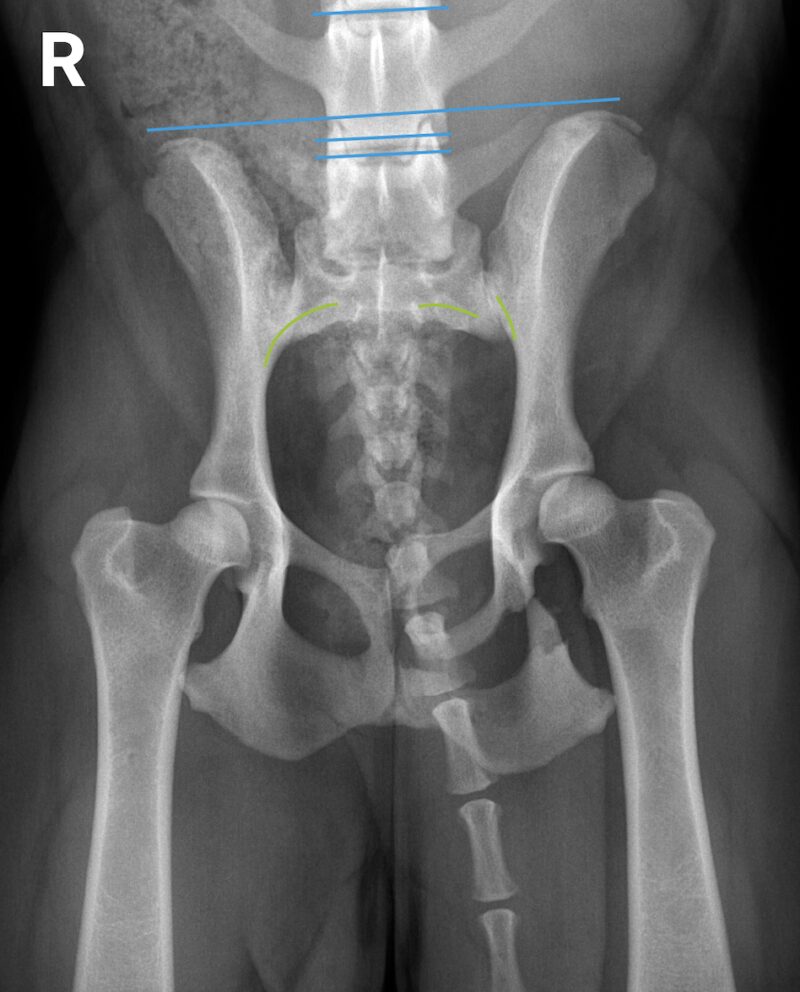

In Folge eines Autounfalls erlitt ein 2 Jahre alter Podenco (weiblich) ein Trauma und kann seitdem nicht mehr gehen. Auch stehfähig ist der Patient nur mit Unterstützung. Der klinische Befund ist links schlechter als rechts. Der Röntgenbefund zeigt eine Schambein- und Sitzbeinfraktur links mit Symphysenfraktur bzw. Symphysiolyse. Zu erkennen ist eine bilaterale iliosakrale Luxation mit langerungsbedingt variabler Darstellung. Die Aufnahmen geben damit Antwort auf die nach einem Unfall häufige Frage, ob das Iliosakralgelenk luxiert ist und eine Diastase vorliegt oder nicht. Eine normale anatomische Situation zeigt stufenlose Gelenkflächenkonturen von Darmbein (Ilium) und Sakrumflügel sowie einen schmalen Gelenkspalt.

• Ein Vergleich der Parallelität einer Tangente entlang der Darmbeinflügel mit Tangenten entlang der Endplatten der kaudalen Lendenwirbel kann leichte Asymmetrien aufdecken helfen.

• Röntgenaufnahmen sind nur Momentaufnahmen und instabile Luxationen können beim Lagern zur bildgebenden Untersuchung (partiell) reponiert werden, wodurch eine Dislokation oder Instabilität manchmal unterschätzt werden kann.

• In diagnostisch unklaren Fällen können komplementäre Röntgenbilder in Position 1 und 2 sowie die CT weiterhelfen.